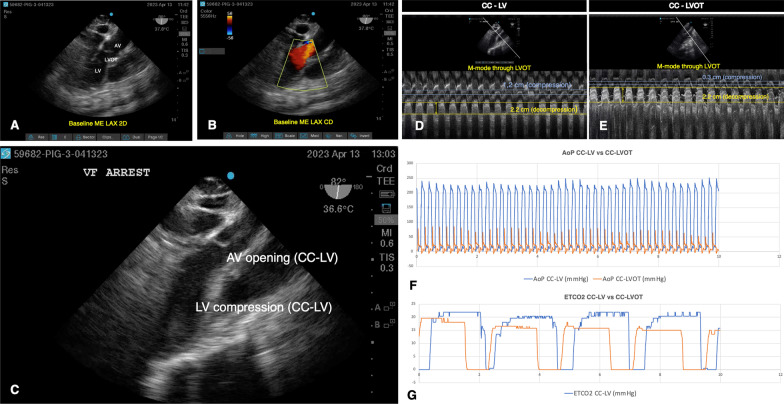

Fig. 1.

Summary of echocardiography and hemodynamic data. A TEE 2D image of midesophageal long axis view (MELAX) during baseline period depicting anatomic structures of interest: the left ventricle (LV), the left ventricular outflow tract (LVOT) and the aortic valve (AV). B MELAX view depicting Color Doppler (CD) through the LVOT. Red color in the Doppler scale corresponds to direction of blood flow from the LV, through the LVOT, and into the ascending aorta. C Shows MELAX image of mid-compression cycle when CCs were being directed to the LV (CC-LV). Anteroseptal wall of the LV is being compressed against the inferolateral wall of the LV and the AV is beginning to open. D and E M-mode image through the LVOT during CC-LV (D) and CC-LVOT (E) with unidimensional measurements of the diameter of this structure during the compression (yellow lines) and decompression (blue lines) phases of CPR. Overlapping hemodynamic measurements corresponding to simultaneous 10 s epochs comparing the two CC locations are shown in F (aortic pressures) and G (ETCO2)

During the CC-LVOT interval phase, we observed near complete closure of the LVOT with concomitant lower AoP and ETCO2. Figure 1 C shows TEE image example of CC-LV where the LV is being targeted, leading to opening of the AV, and representing the “ideal” CC location. Images D and E are M-mode images through the LVOT generated from video clips corresponding to each CC location interval. Overlapping aortic pressures (F) and end-ETCO2 (G) of simultaneous 10 s epochs comparing the two CC locations are presented. During intervals of CC-LV we consistently observed higher AoP and end-tidal CO2 (ETCO2). During compressions directed over the LV, we observed patency of the AV and Color Doppler (CD) reflecting flow through the LVOT (Fig. 1F, G).